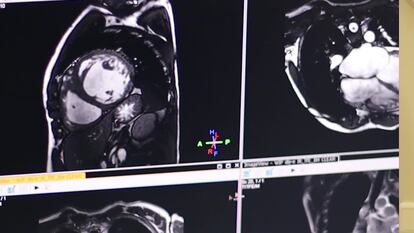

Alrededor de un 25% de las personas con un cáncer que reciben tratamientos con antraciclinas, los quimioterápicos más usados, desarrollará dolencias cardiacas. Detectarlas lo antes posible es fundamental para evitar que, literalmente, el remedio sea peor que la enfermedad. E investigadores del Centro Nacional de Investigaciones Cardiovasculares (CNIC) han descubierto lo que definen como el método de diagnóstico más precoz: una prueba de imagen (una resonancia magnética) que detecta sus primeras manifestaciones, que son edemas (hinchazones) de agua intracelular.

Para el estudio, los investigadores han usado cerdos, el modelo animal con el corazón más similar al humano, tanto que se ha planteado varias veces usarlo para trasplantes. Se les inyectó el fármaco, y se les hicieron resonancias cardiacas hasta descubrir la lesión utilizando la denominada T2 mapping, una metodología de resonancia magnética cardíaca.